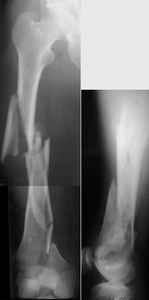

I presented a series of ~25 such cases at EuroTrauma'2004. Many cases were discussed here. I attach am example. Look also recent cases at http://www.hwbf.org/hwb/conf/alex58/scfx.htm,

http://www.hwbf.org/hwb/conf/alex63/alex63.htm